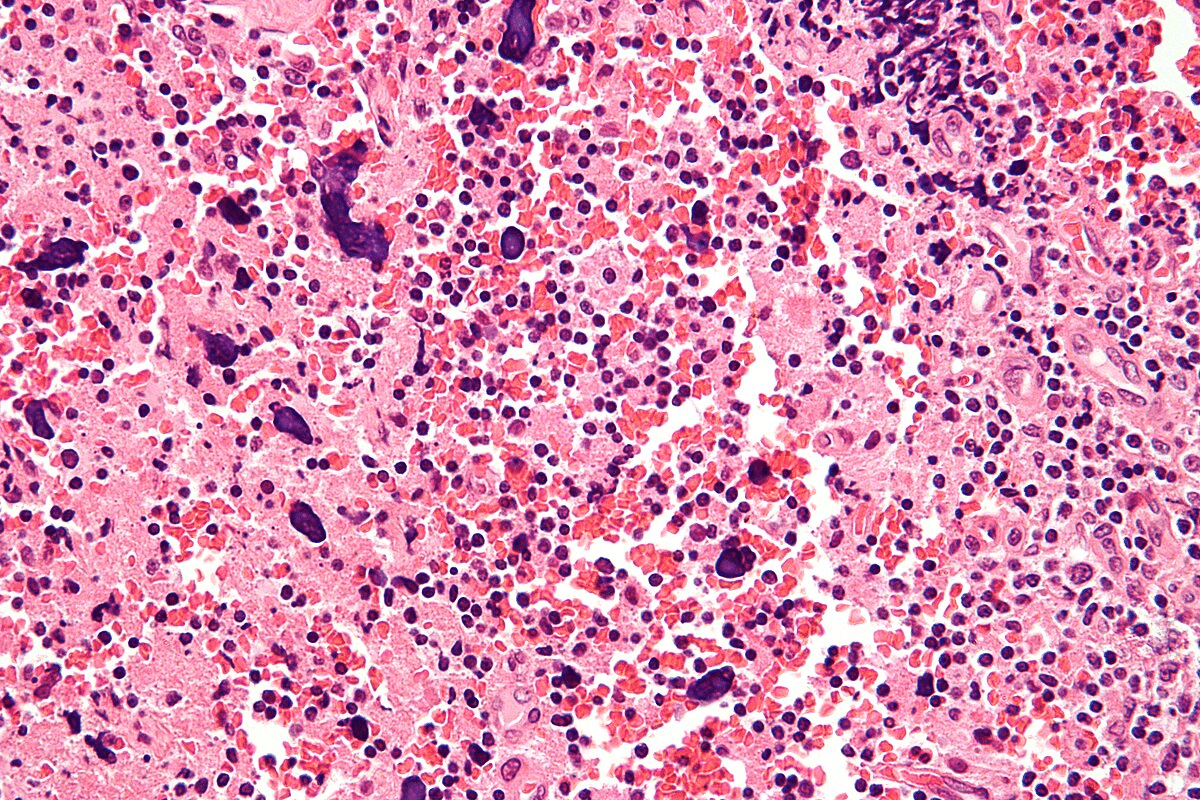

Mechanism 7: Tissue Deposition of Immune Complexes

In SLE, immune complexes in tissues start a chain of inflammatory reactions. This affects many organ systems. It’s key to understanding how lupus impacts different organs and tissues.

Multi-System Inflammatory Patterns

When immune complexes settle in tissues, they activate immune cells. This leads to the release of pro-inflammatory cytokines. As a result, inflammation spreads across multiple organs, like the kidneys, skin, and joints.

Autoantibodies also play a role. They form immune complexes that settle in tissues. This cycle of inflammation and tissue damage makes SLE complex.

Organ-Specific Manifestations

SLE’s effects on different organs vary. For example, kidney problems are a serious issue due to immune complex buildup in the glomeruli.

SLE can also cause skin rashes and lesions, and affect the muscles, leading to arthritis and myositis. The wide range of organ involvement shows the importance of a detailed approach to treating SLE.